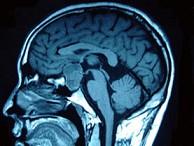

问题 男,47岁,头痛三年余,最近2个月感觉视力下降,MRI检查如图,最可能的诊断为()

选项 A.垂体瘤 B.颅咽管瘤 C.垂体囊肿 D.垂体腺瘤囊变 E.脑膜瘤

答案 D